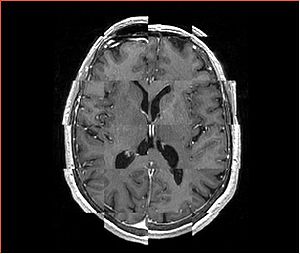

• Checkerboard appearance of unregistered images for the representative data of interest

• Case01